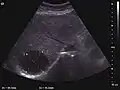

Liver cysts

They can be single or multiple, with variable size, generally less than 20 mm (congenital). Rarely, sizes can reach several centimeters, leading up to the substitution of a whole liver lobe (acquired, parasitic). They may be associated with renal cysts; in this case the disease has a hereditary, autosomal dominant transmission (von Hippel Lindau disease).

The ultrasound appearance is a well defined lesion, with very thin, almost unapparent walls, without circulatory signal at Doppler or CEUS investigation. The content is transonic suggesting fluid composition. The presence of membranes, abundant sediment or cysts inside is suggestive for parasitic, hydatid nature. Posterior from the lesion the acoustic enhancement phenomenon is seen, which strengthens the suspicion of fluid mass. They typically displace normal liver vessels but no vascular or biliary invasion occurs.